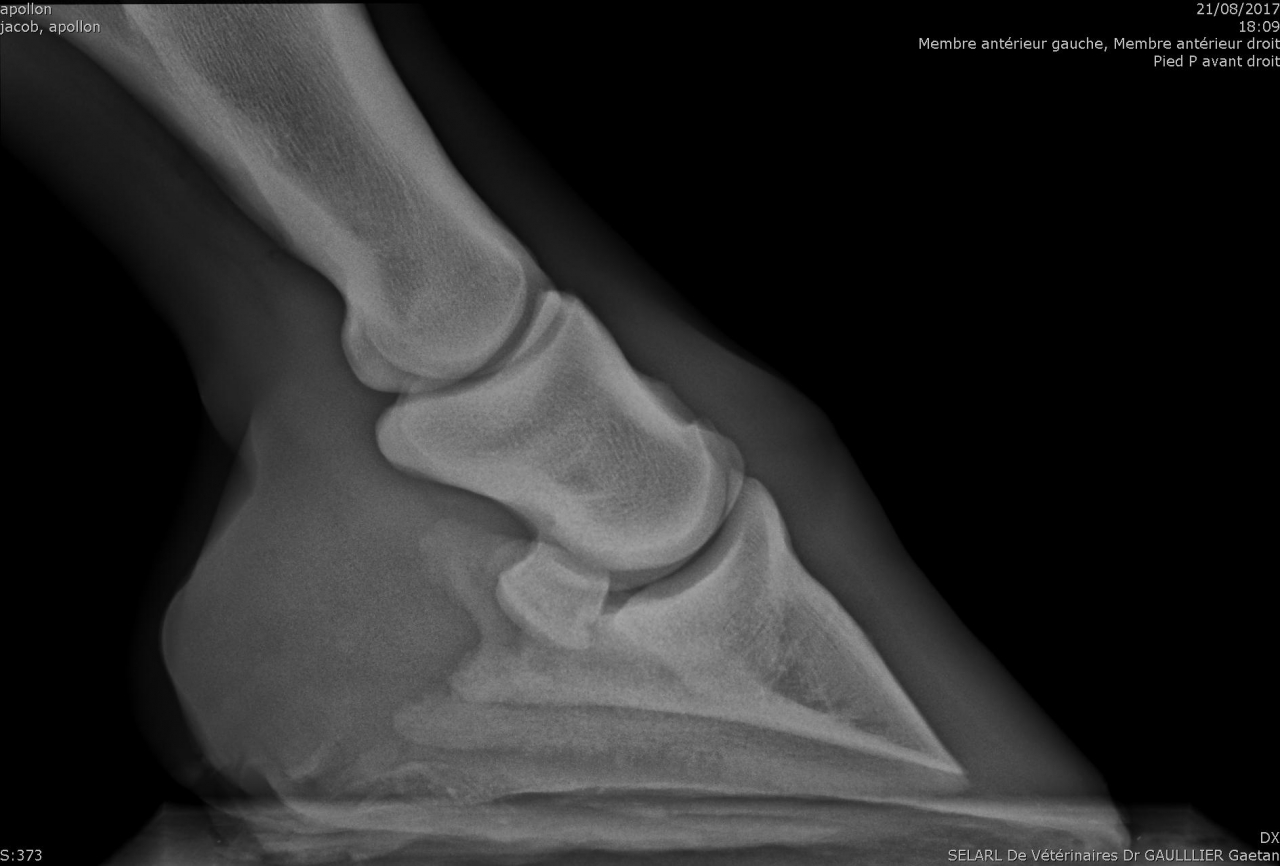

| Dire merci | Alors pour les fers, je ne suis pas une ayatollah du pieds nus, donc je l'ai évoqué avec la véto. Selon elle à ce stade, ça ferait plus de mal que de bien, pour les raisons suivantes : - jument confortable au pré, puisque terrains bien mous en ce moment - difficulté à ferrer vu ce qu'il "reste de pied", elle pense que ça va être un calvaire pour la jument de clouer - si jamais c'est un soucis de vascularisation, ça va plutôt amplifer le soucis Concernant les PHW, justement avec Kaline on était passé à une orthopédie à base de PHW, parce que pas moyen de faire tenir des fers compensés en talon dans la boue. Après ça dépend beaucoup de la locomotion du cheval, mais vu que Cam' n'est pas une foudre de guerre et que même si le pré est boueux on ne s'enfonce pas tant que ça, je suis plutôt confiante. Pour la biotine je veux bien des infos. Moi on m'a souvent dit que ça rendait l'organisme "paresseux" pour en produire lui même, et que si la flore digestive et les apports nutritionnels sont ok y a pas de raison d'avoir de carence ? J'aurais donc plutôt tendance à agir là dessus ? Les radios en spoilers pour celles et ceux que ça intéresse. Message édité le 19/02/18 à 17:18 |

| Dire merci | Elle a des radios moins pire que le mien quand même, et pourtant le MF n'a eu aucun mal à la ferrer ![]() Il a juste broché haut, et pas de raison qu'il y ait de douleurs au ferrage ![]() Par contre, le mien avait les pieds moins petits que la petite en proportion, et pourtant il me parait plus fin... |